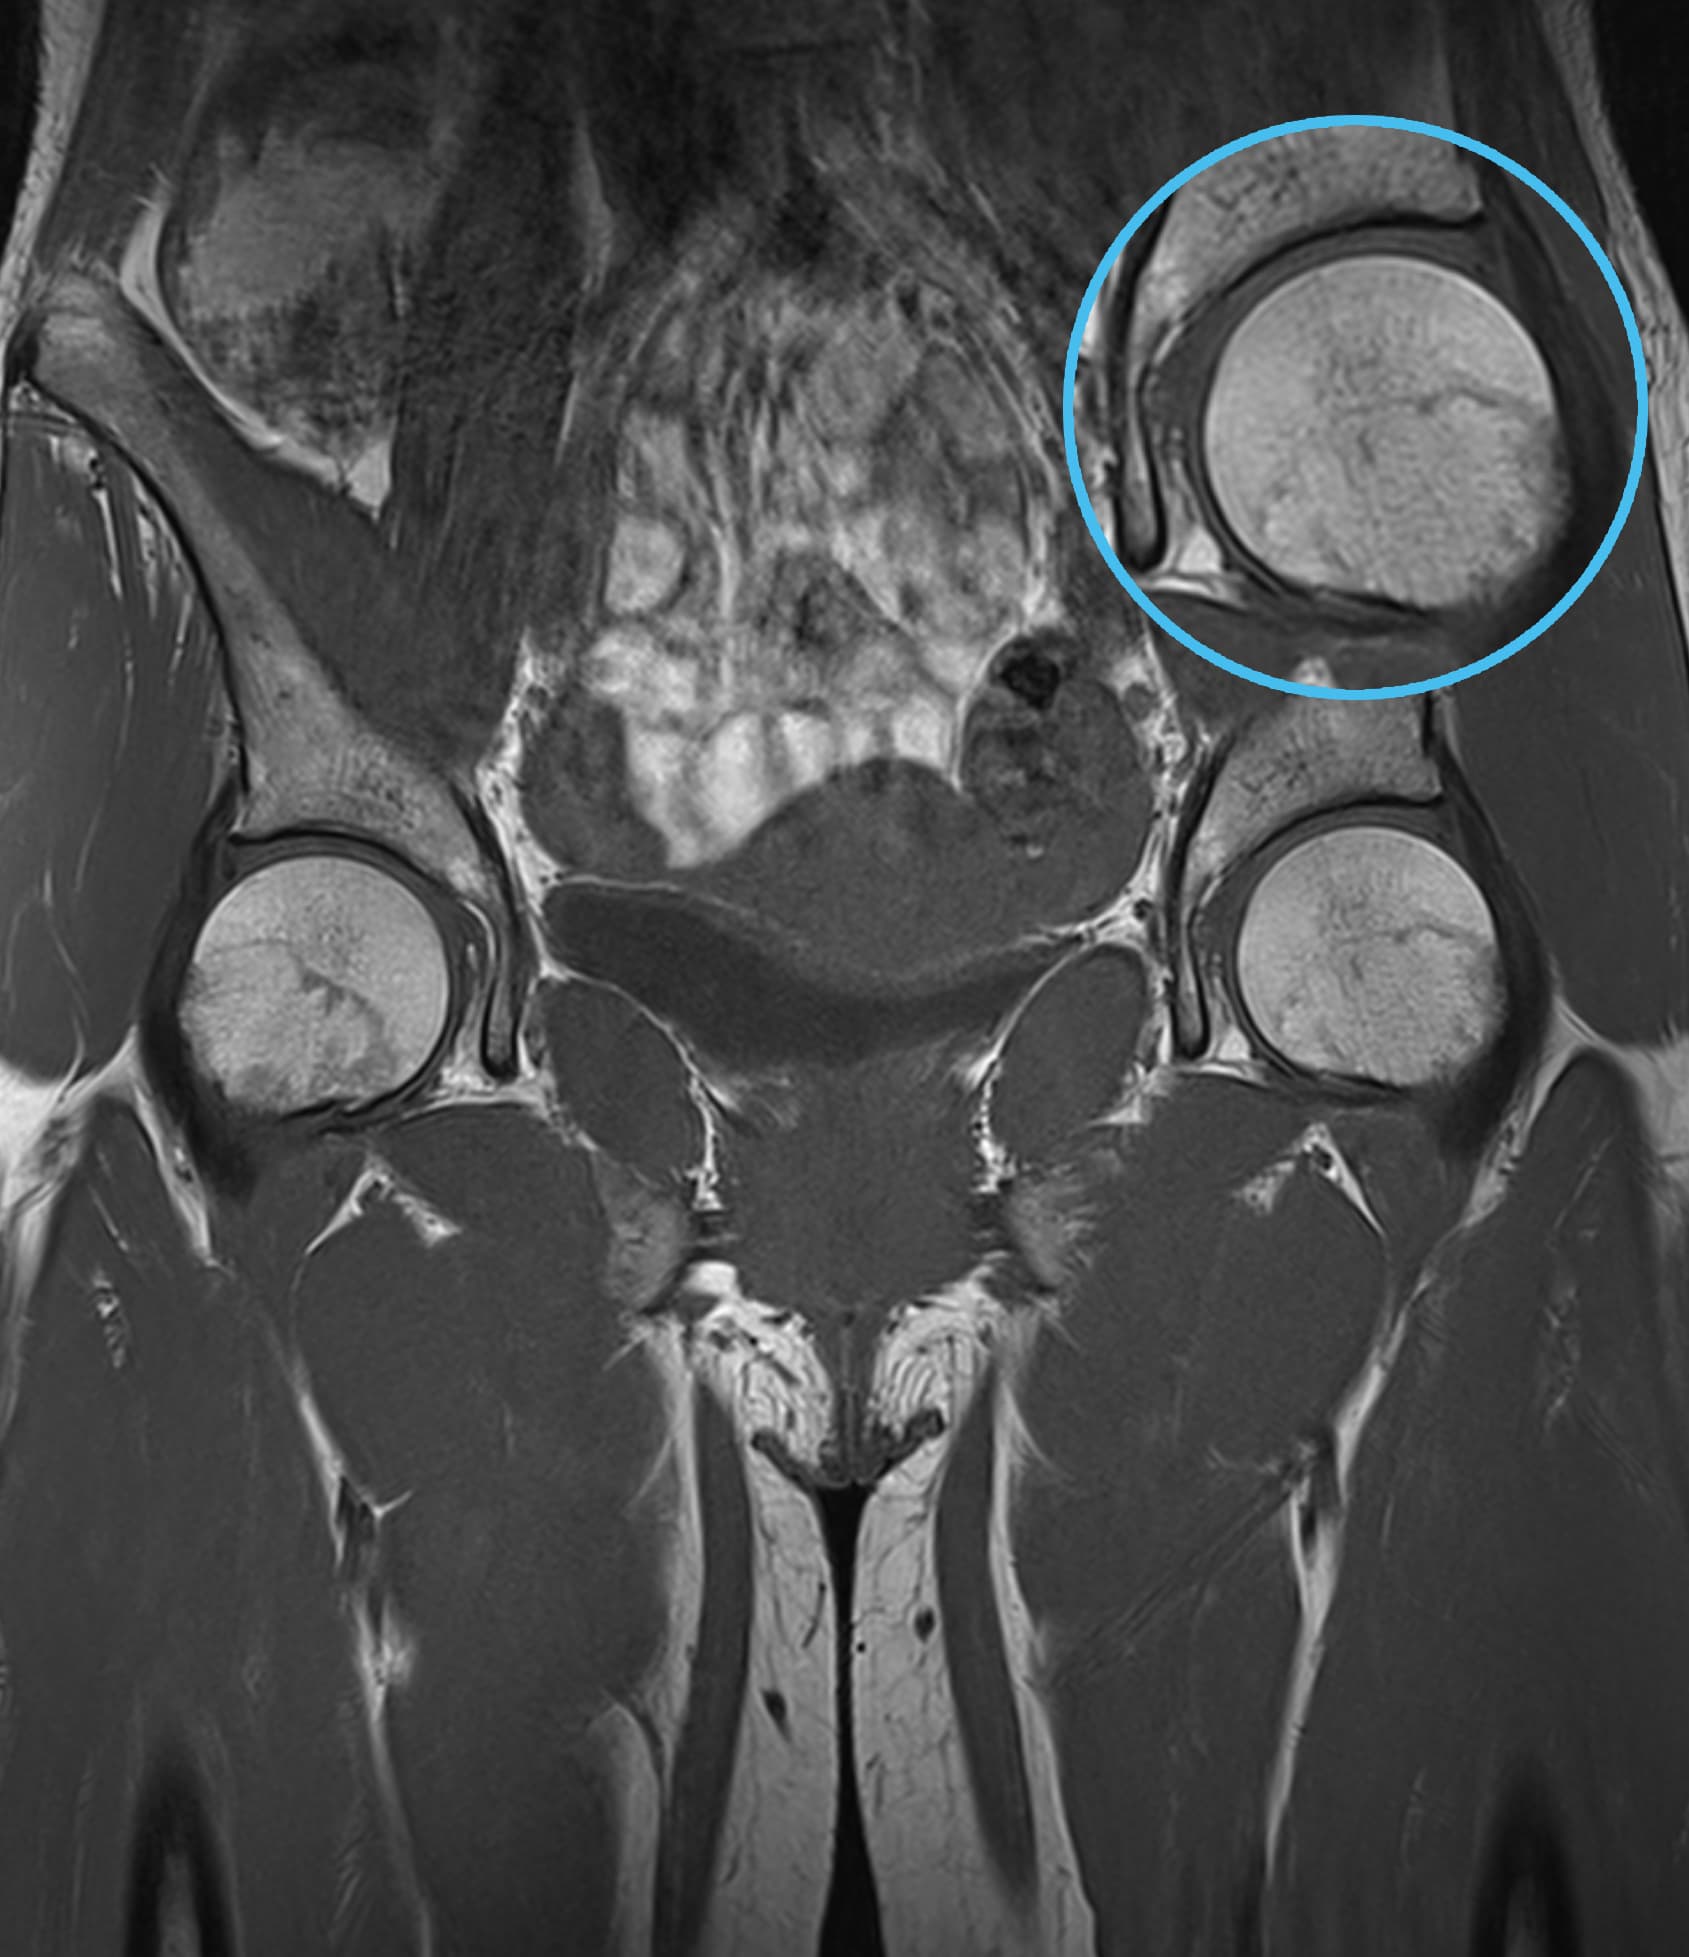

Δείτε πραγματικά παραδείγματα του SwiftMR™ σε διάφορα συστήματα MRI και ανατομικές περιοχές

Scan time 03:14

Scan time 02:07

Scan time 03:08

Scan time 1:12

Scan time 04:53

Scan time 1:46